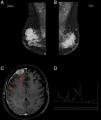

(A and B) Mammography: hyperdense and lobulated nodules with circumscribed margins; (C) extra-axial expansive lesion compatible with plasmocytoma in the right frontal convexity (arrow) with pachymeningeal impregnation (arrowhead), demonstrating central nervous system involvement; (D) spectroscopy of the same patient showing an increased glutamine–glutamate complex (arrow) resulting from elevated central nervous system ammonia.

The patient underwent induction chemotherapy with the administration of the CTD regimen (cyclophosphamide, thalidomide, and dexamethasone). After three cycles, her clinical condition worsened with altered level of consciousness, seizures, and disease progression with new plasmacytomas (sternum and central nervous system−CNS) and hyperammonemia being observed. This metabolic change was established by measuring the serum ammonia level (93μmol/L; normal value up to 32μmol/L) and confirmed by proton magnetic resonance spectroscopy (PMRS), which showed a glutamine/glutamate peak and reduced choline and myo-inositol (Figure 1).